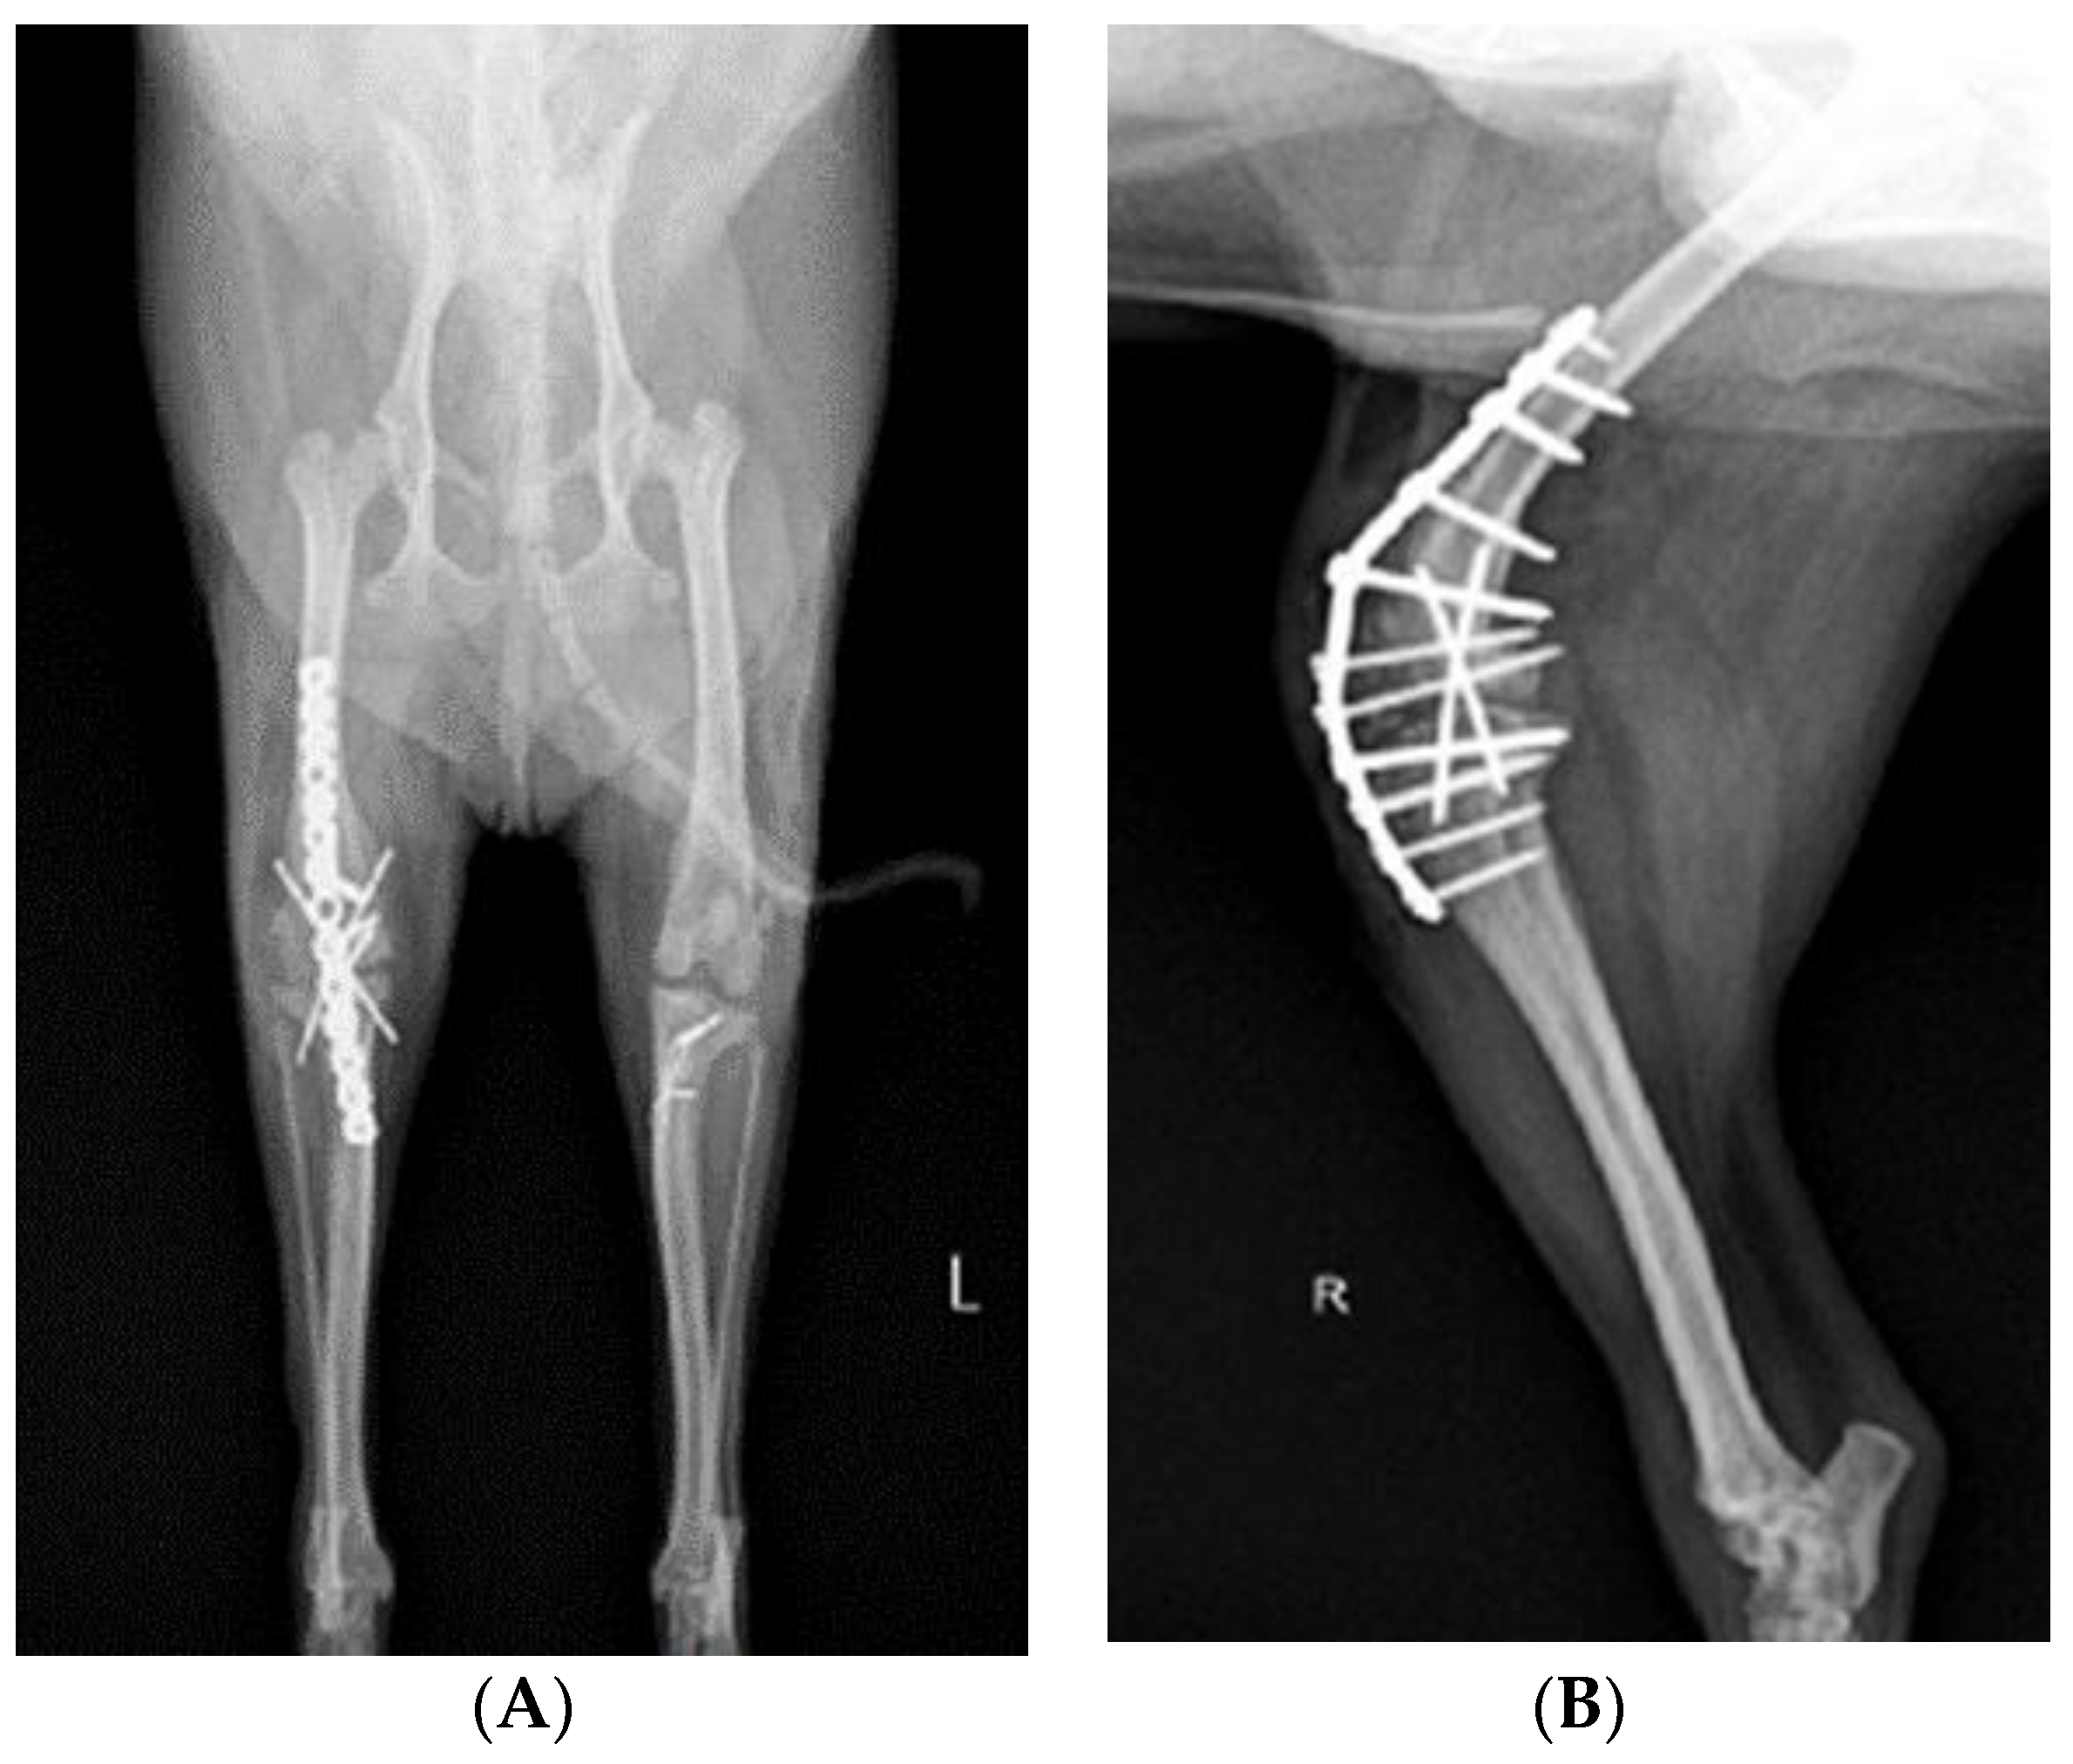

Before surgery, antibiotic and anti-inflammatory drugs were applied for about a month to relieve pain, edema, and arthritis; then, the surgery was performed. For treatment, amoxicillin/clavulanic acid (12.5 mg/kg, Amocla, KUHNIL corp., Seoul, Republic of Korea), carprofen (2.2 mg/kg, RIMADYL, Zoetis Inc., Parsippany-Troy Hills, NJ, USA), tramadol (2 mg/kg, Tridol cap. Yuhan Corp, Seoul, Republic of Korea), and famotidine (0.5 mg/kg, Famotidine, Hanmi Pharm, Seoul, Republic of Korea) were prescribed BID for 4 weeks. After one month, radiographic findings confirmed that inflammation and edema in both stifle joints were reduced (Figure 2). The owner was informed that stifle joint arthrodesis was to be performed on the right hind limb due to severe osteoarthritis, loss of the patella, and rupturing of the cranial cruciate ligament and that MPL correction was to be performed on the left leg. Accordingly, the consent of the guardian was obtained.

Figure 2.

Preoperative craniocaudal (A) and mediolateral (B,C) radiographs of the right and left stifle joints. The prescribed anti-inflammatory drugs reduced pain, lowered fever, and decreased inflammation (swelling and damage) after about a month. Arrows in images show areas with significantly reduced inflammation and edema compared to a month prior.